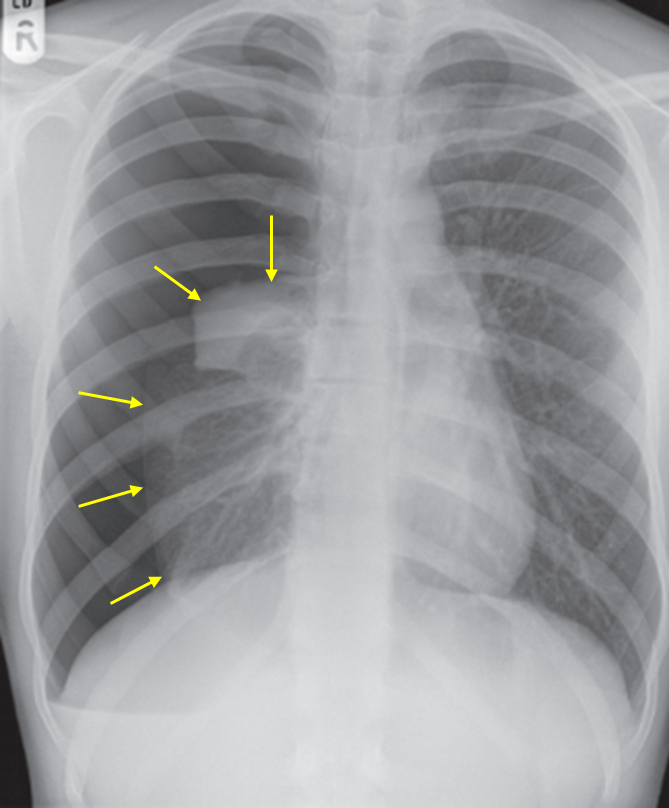

18세 남자가 3일 전부터 숨이 찬다며 응급실에 왔다. 혈압 98/65 mmHg, 맥박 100회/분, 호흡 24회/분, 체온 36.6°C이다. 피부경유산소포화도는 93%이다. 가슴 청진에서 오른쪽 가슴의 호흡음이 들리지 않는다. 가슴 X선 사진과 심전도이다. 가능성이 큰 진단명을 고르시오 (두 가지).

Img | CXR: Rt. lung near-total collapse, loss of distal vascular markings |

• CXR에서 우측 폐의 near-total collapse가 보이며 distal vascular marking이 소실되었으므로 기흉이 의심된다. 환자가 젊고 특이 병력이 없으므로 PSP가 가장 의심된다.

검사소견 | • CXR: Pleural line 보임, vascular marking이 보이지 않음 |